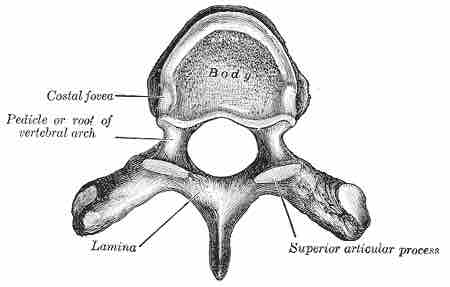

The twelve thoracic vertebrae are located inferiorly to the cervical region. They are larger than the cervical vertebrae and increase in size moving inferiorly to the lumbar region.

Thoracic vertebra

Image of a typical thoracic vertebra.